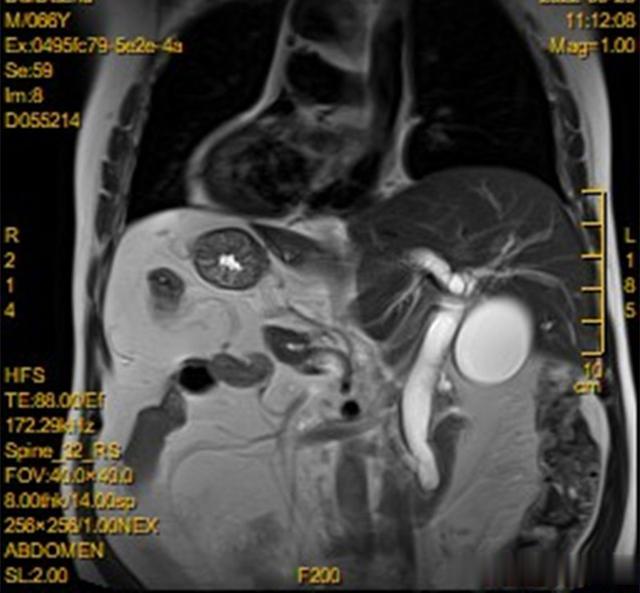

“镜面人”又称“镜子人”或“镜像人” , 即心脏、肝脏、脾脏、胆等器官的位置与正常人相反 , 心脏、脾脏在右边 , 肝脏位于左边 , 心、肝、脾的位置好像是正常脏器的镜中像 。 日前 , 安医大二附院就接诊了这样一位特殊的伴有血管解剖变异的镜面人患者 , 经过12小时的手术 , 医生为这位患者成功切除了12指肠肿瘤 。 据悉 , 该类手术在国内外文献中均罕见报道 。

据了解 , 今年66岁的戴先生近1个月来出现了眼黄和尿黄的症状 , 出现症状后他随即到了家附近的医院就诊 , 当地医生告诉戴先生 , 他可能患上了12指肠肿瘤 , 需要手术治疗 。 戴先生辗转来到了安医大二附院住院寻求手术治疗 , 在该院肝胆胰外科三病区 。 接诊医生给戴先生安排了检查 , 当腹部CT检查结果出来时 , 科室医生惊奇的发现 , 这是一位非常罕见的“镜面人”患者 , 发病率仅为百万分之一 。

医生经过进一步诊察发现 , 戴先生的肿瘤生长在一个被称为“12指肠乳头”的部位 , 肿瘤的生长已经引起了胆道的梗阻 , 而且患者的血管也有明显的解剖变异 。 病区主任侯辉立即组织了医疗组展开治疗方案的研判 , 经过反复讨论 , 治疗组明确了手术切除胰头和12指肠的最佳治愈手段 。